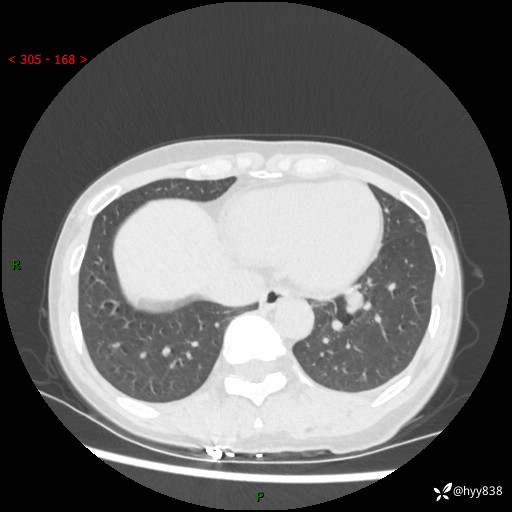

【患者信息】:55岁/女

【主诉】:咳嗽咳痰半月,发现肺占位2天

【现病史及既往史】:患者半月前出现咳嗽咳痰,伴头晕胸闷、无发热气喘。于当地医院住院行抗感染治疗1周(具体药物不详),后咳嗽减轻,但仍未完全缓解,复查胸部CT示:左肺下叶1.8*1.2结节软组织影。为求进一步诊治来我院,门诊以“肺占位”收入院。 自患病以来,精神、饮食、睡眠尚可,大小便正常,体力体重无明显减少。

【检查】:胸部CT平扫+增强

各期CT值:40hu 57hu 49hu